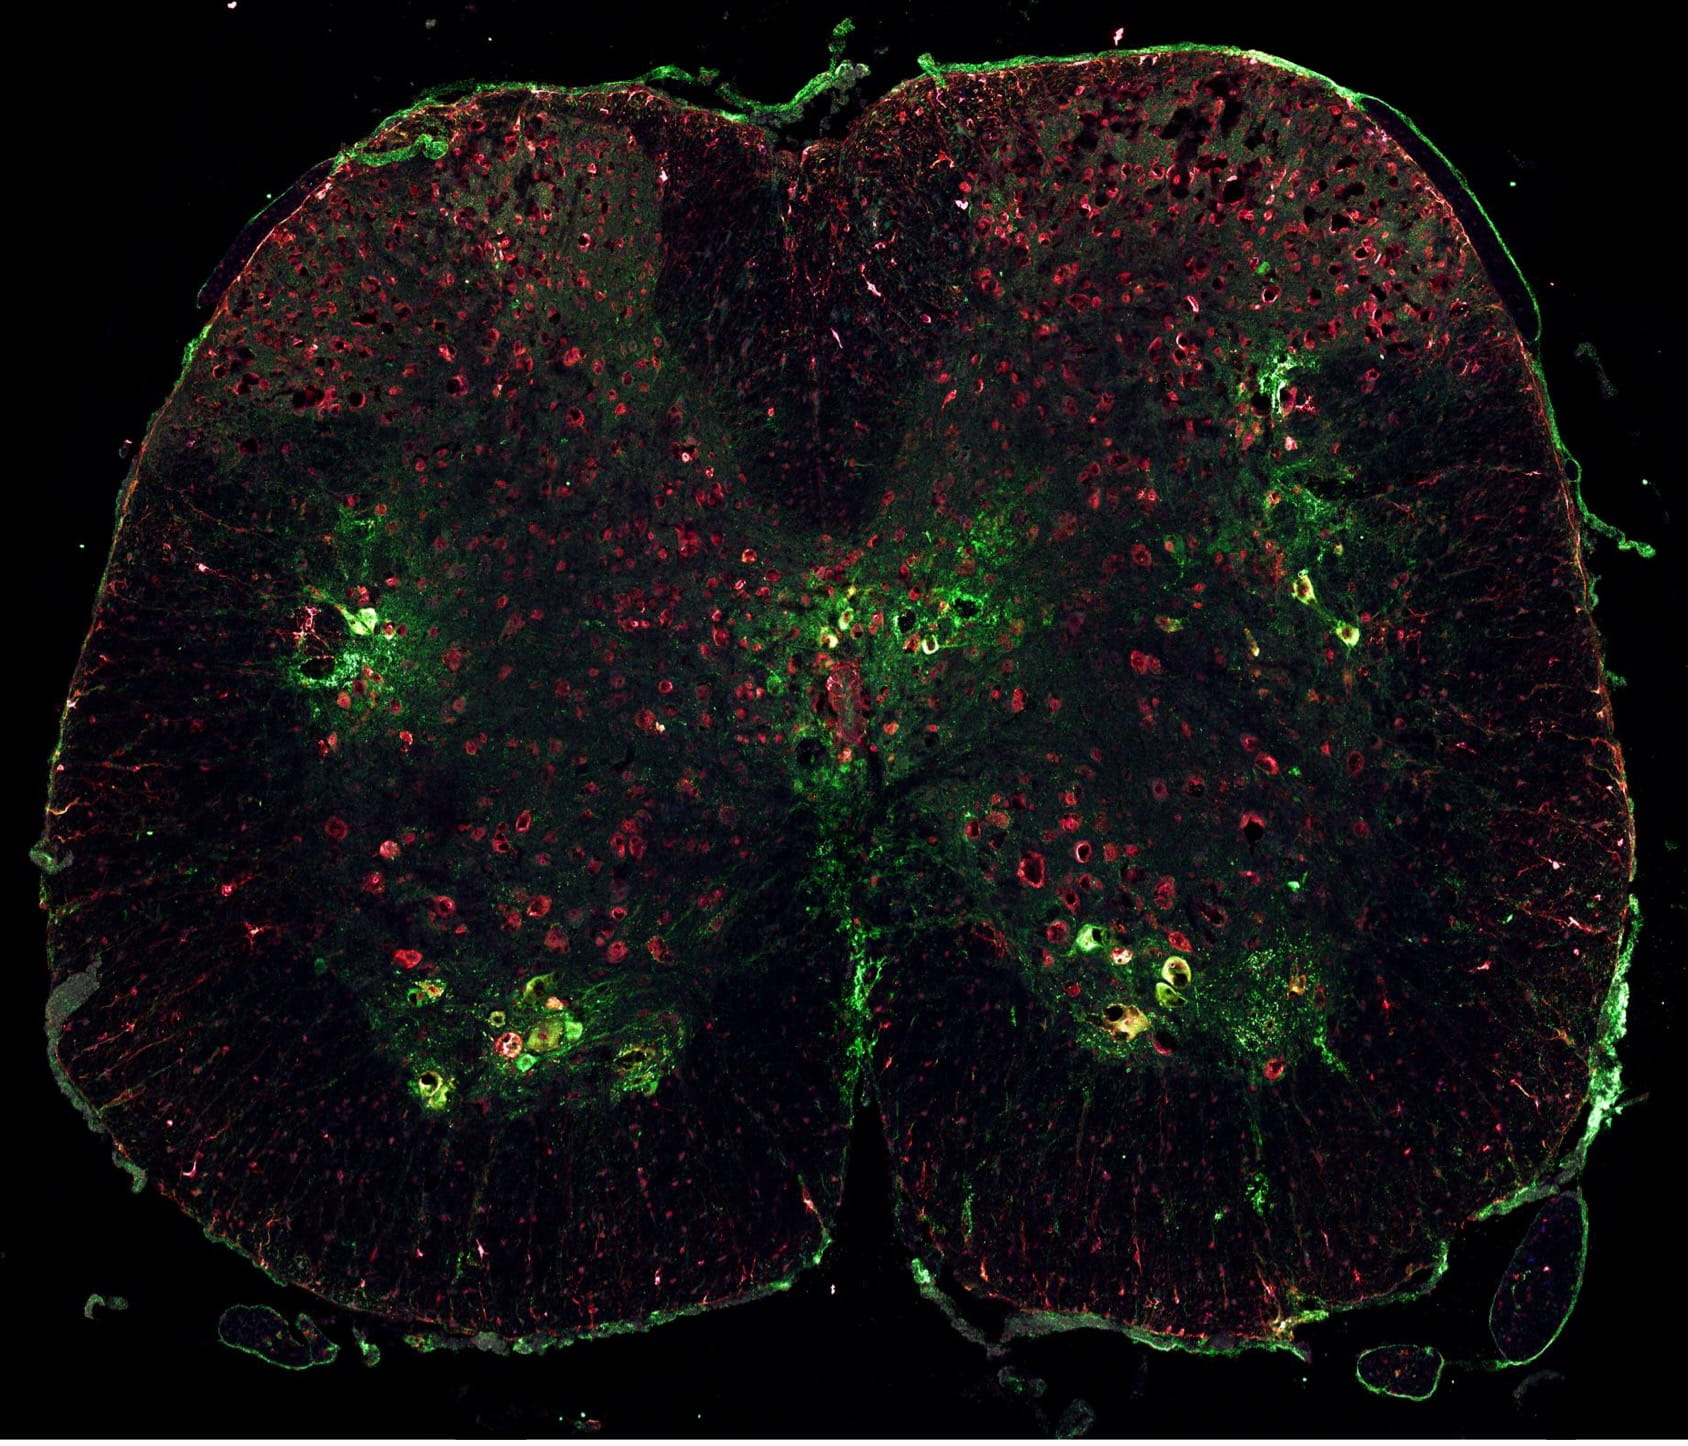

Cross section image of the spinal cord in ALS mouse model with green indicating neurons and red indicating proteins involved with ALS“The peripheral motoneuron is one of the largest and most complex of cells in the human body,” Jones said. “It has widespread connections with all parts of the brain and spinal cord, as well as virtually all the skeletal muscles of the body. Such complexity makes it extremely challenging to pinpoint underlying causes of ALS.”